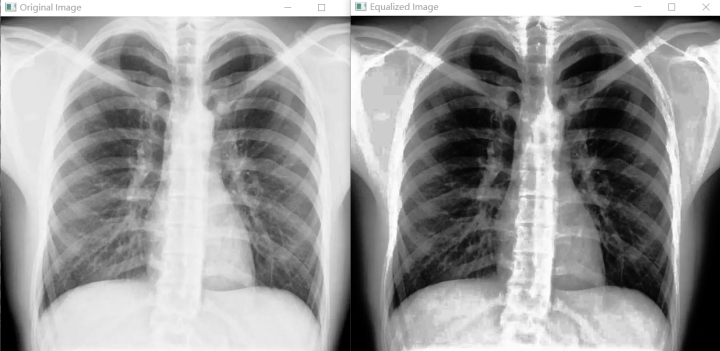

直方图均衡化(Histogram Equalization)是一种增强图像对比度(Image Contrast)的方法,其主要思想是将一副图像的直方图分布变成近似均匀分布,从而增强图像的对比度。直方图均衡化的核心目标是通过调整图像的灰度分布,使图像的亮度分布更加均匀,从而提升图像的对比度。其基本思想是将原始图像的直方图通过一种映射函数转换为均匀分布的形式。

增强图像对比度 - 原理:通过重新分配像素灰度值,使原本集中在狭窄范围内的灰度分布变得广泛且均匀,从而拉伸图像的动态范围。 - 效果:提升暗区或亮区的细节可见性,例如医学影像中隐藏的病灶或卫星图中细微的地形差异。

代码示例:

cv2.imshow('Original Image', image)

cv2.imshow('Equalized Image', equ_image)